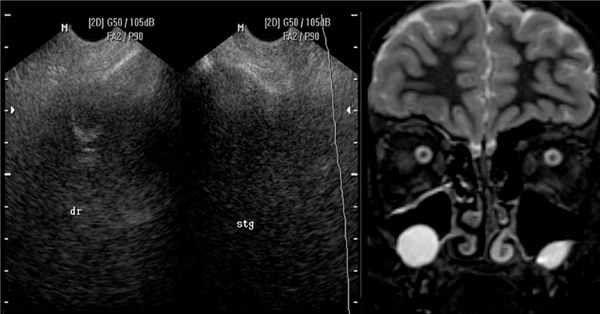

На рентгеновском снимке о наличии кисты можно говорить в случае, если в проекции пазухи имеется затемнение с краем, который может являться частью круга. Центр данного круга должен при этом находиться внутри пазухи, а не за ее пределами – в таких случаях речь идет, скорее, о наличии жидкости в пазухе (вязкого характера) или об ином экссудативном процессе. На рентгенограммах пазух кисты могут давать и картину тотального затемнения пазухи – в этом случае необходима дифференциальная диагностика с экссудативным гайморитом, муко- и пиоцеле, опухолью и т. д. На рентгенограмме определяются кисты верхнечелюстных пазух с обеих сторон. Обратите внимание на верхний край затемнения в пазухах – он ровный, имеет полукруглую форму, характерный для кист вид. В данном случае с целью уточнения размеров и локализации кист необходима компьютерная томография околоносовых пазух. Характерная для кисты верхнечелюстной пазухи картина при компьютерной томографии: обратите внимание на объемное образование в правой гайморовой пазухе, которое имеет ровные, закругленные края (отмечены стрелкой красного цвета), однородную структуру и плотность, соответствующую жидкости (+5…+15 единиц по шкале Хаунсфилда). Видно также, что выводной проток пазухи сужен, слизистая ячеек этмоидальной пазухи с правой стороны утолщена, имеет место утолщение слизистой носа – все это признаки катарального этмоидита, ринита, возникшего вследствие нарушения мукоцилиарного клиренса. Не путайте кисту верхнечелюстной пазухи с пролабирующим в полость пазухи корнем зуба (отмечен стрелкой) – на рентгенограммах очень часто тень зуба дает картину, имитирующую кистозное образование в пазухе – зачастую только с помощью КТ пазух можно различить эти два состояния. На данных изображениях также представлена киста гайморовой пазухи справа – обратите внимание на аксиальный срез (слева). Только по одному аксиальному срезу сложно сделать вывод о том, что за образование находится в полости пазухи, однако при выполнении реформаций в сагиттальной плоскости можно убедиться, что это именно киста большого размера (по характерному для кисты ровному закругленному краю, отмеченному стрелкой). Также на изображении справа видно, что слизистая оболочка гайморовой пазухи справа утолщена, а в ячейках решетчатой кости с этой же стороны визуализируется содержимое в большом количестве, выводные протоки гайморовой и этмоидальной пазух не прослеживаются. В данном случае наличие большой кисты в гайморовой пазухе спровоцировало развитие воспалительной реакции слизистой и явилось причиной правостороннего этмоидита. На изображениях можно проследить следующую патологию – часть этмоидальной пазухи пролабирует в полость носа (пролабирующая ячейка заполнена содержимым жидкостного – исходя из ее плотности – характера; отмечена стрелкой). Утолщена также слизистая верхнечелюстных пазух, резко сужены их выводные протоки (отмечены цифрой 1 на левом скане). На изображениях в аксиальной плоскости (слева), сагиттальной (в центре) и корональной (справа) плоскостях видна киста правой гайморовой пазухи. На КТ она выглядит как образование с ровными краями, жидкостной плотности (обозначена на всех сканах красными стрелками). На крайнем правом скане также цифрой 1 обозначена правая половина этмоидальной пазухи, заполненная содержимым. Имеются также признаки катарального гайморита (на левом скане) – оцените слизистую оболочку левой гайморовой пазухи – она явно утолщена. Небольшая киста гайморовой пазухи на КТ справа. Отмечена стрелками. Располагается пристеночно у задних отделов медиальной стенки и нижней стенки пазухи. Не вызывает нарушений отхождения слизистого секрета из пазухи.